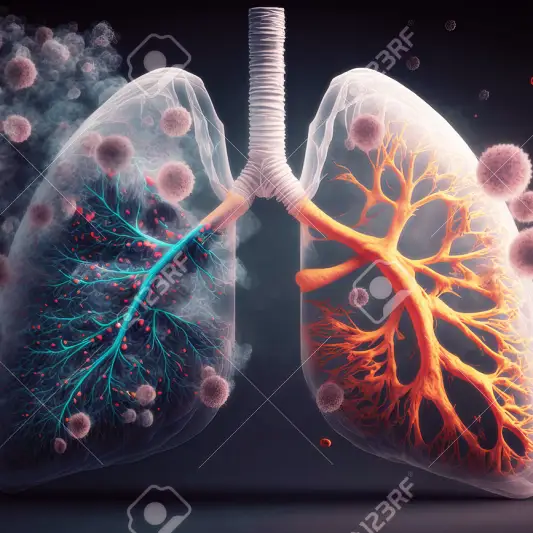

폐암 수술 후 필요한 관리와 후송 기간

폐암 수술은 환자들에게 많은 노력과 인내를 요구합니다. 수술 후에는 적절한 관리와 후송 기간이 필요합니다. 환자가 빠른 회복을 위해 지켜야 할 몇 가지 중요한 사항이 있습니다. 올바른 관리와 적절한 후송은 환자의 치료와 회복에 큰 도움이 될 것입니다.

많은 사람들이 수술 후에는 회복과 체력 관리에 많은 노력을 기울입니다. 특히 폐암 수술 후에는 더욱 필요한 관리와 후송 기간이 있는데요. 이 글에서는 폐암 수술후 필요한 관리와 후송 기간에 대해 알아보겠습니다.